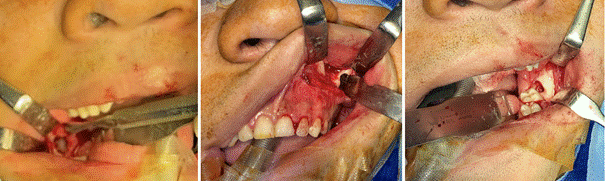

Bajo anestesia general, con intubación orotraqueal, se realizó la enucleación de las lesiones mandibulares, curetaje/osteotomía periférica con posterior aplicación de SCM por 3 minutos, y se instaló cánula descompresiva en lesión maxilar izquierda, la cual se mantuvo permeable y con indicación de lavados diarios con clorhexidina al 0.12% hasta lograr una descompresión adecuada para realizar su posterior enucleación (Figura 3). Actualmente el paciente se mantiene en control clínico mensual, y radiológico cada 6 meses.